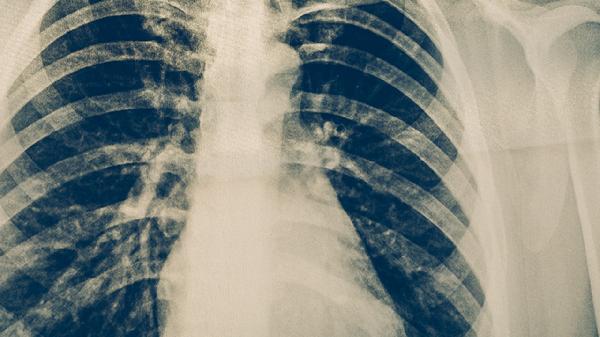

肺炎通常分为细菌性肺炎、病毒性肺炎、支原体肺炎、真菌性肺炎和吸入性肺炎五种类型。不同类型的肺炎在病因、症状及治疗方式上存在差异,需结合具体病原体和临床表现进行针对性处理。